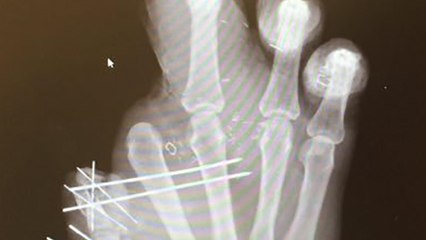

It has been confirmed that New York Giants defensive end Jason Pierre-Paul lost part of his right thumb, in addition to his index finger during a fireworks accident on the Fourth of July. Pierre-Paul has been working out trying to get back, even though publicly it seems like another finger falls off each month. But the two-time Pro Bowler fired back at his critics by posting a video of him working out without gloves. By the looks of it, his right hand is only slightly bandaged.